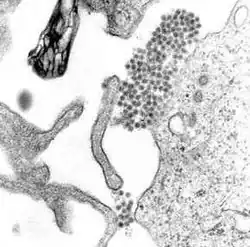

Imagine a virusului denga la microscopul electronic cu transmisie

Imagine mărită a virusului denga (grupul de puncte întunecate din centru)

Febra denga este provocată de virusul cu același nume. În sistemul de clasificare și nomenclatura virusurilor, virusul denga face parte din familia Flaviviridae, genul Flavivirus. Din această familie fac parte și alte virusuri care pot provoca boli în rândul oamenilor. De exemplu, virusul febrei galbene, virusul West Nile, virusul encefalitei St. Louis, virusul encefalitei japoneze, virusul encefalitei de căpușă, virusul bolii Kyasanur forest și virusul febrei hemoragice Omsk aparțin tot familieiFlaviviridae.[8] Cele mai multe dintre aceste virusuri sunt răspândite de țânțari sau căpușe.[8]